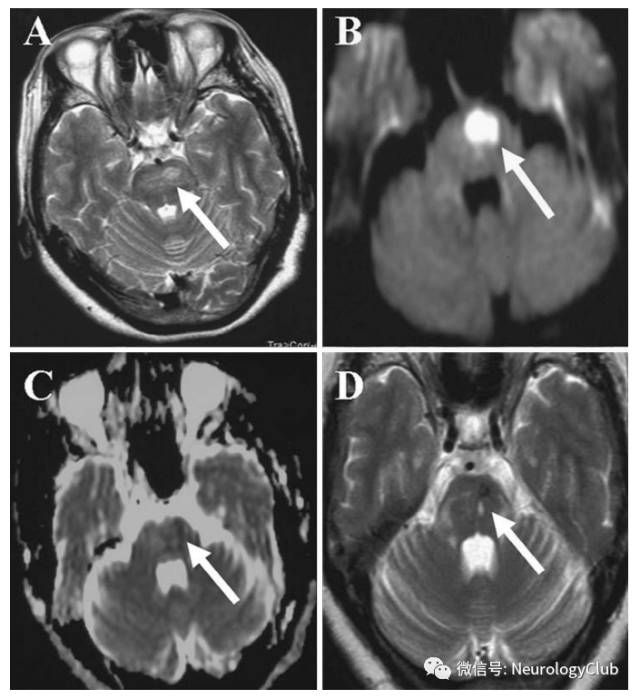

脑实质病变

(图12:貌似脑梗死的神经白塞病,可见T2WI高信号病灶,DWI上弥散受限,对应ADC呈低信号)

(图13:A:T2WI可见左侧脑桥高信号病灶;B:DWI弥散受限;C:ADC呈低信号;D:治疗后5月复查T2WI较前好转)